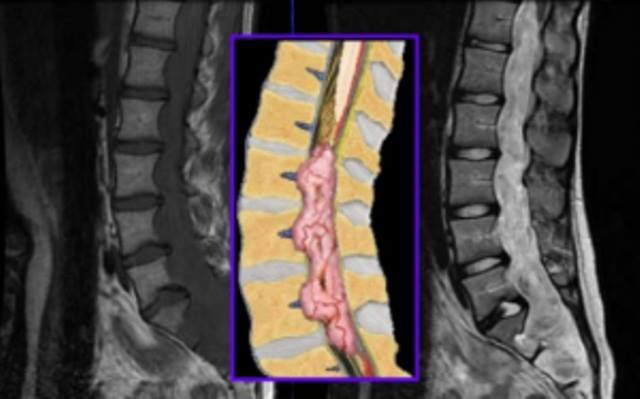

| Hình ảnh u màng nội tủy nhầy nhú trên phim cộng hưởng từ T1 và T2. |

Bệnh nhân được chụp phim X-quang cột sống thắt lưng thường quy và chụp cộng hưởng từ cột sống thắt lưng có tiêm thuốc cản quang. Kết quả phim cộng hưởng từ cho thấy, u tủy sống chiều dài hai thân đốt L1L2, khối u ranh giới rõ, chiếm toàn bộ lòng ống tủy, chèn ép trực tiếp vào chóp tủy. Trước ca bệnh này, các bác sĩ đã chỉ định mổ vi phẫu thuật lấy toàn bộ khối u tủy.